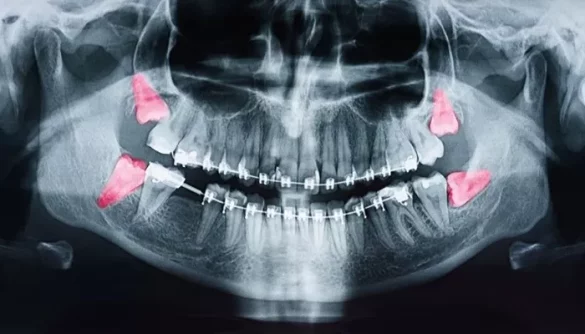

Wisdom teeth can also become impacted due to abnormal growth patterns. Instead of erupting straight up and down like other teeth, they may grow at angles or even horizontally.

Angled Eruption: Often referred to as mesial or distal impaction, this occurs when a wisdom tooth grows toward the front or back of the mouth instead of vertically. Such angled growth can lead to pressure on neighboring teeth and cause pain or discomfort.

Partial Eruption: Sometimes wisdom teeth only partially emerge through the gums. This situation can create pockets where bacteria can thrive, leading to infections and other complications such as pericoronitis (inflammation of the gum tissue surrounding a partially erupted tooth).